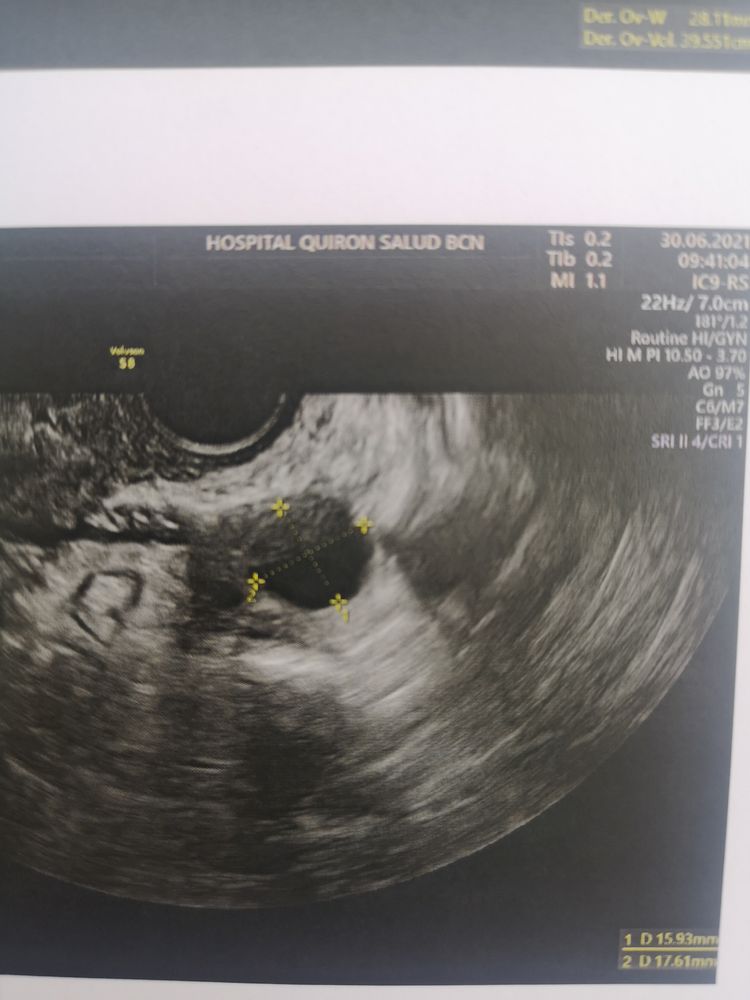

Девочки очень интересуют ваше мнение. Ситуация такая у меня ранней О не бывает, самая ранняя была за полтора года планирования на 12 дц. Обычно 14-16 дц. В пя раньше в ля позже. Сегодня 12 дц с 9 дц делаю тесты на О, тесты мне всегда отлично показывают О. Тесты никакие. Меряю бт и она растёт. По ощущениям О не было, выделения яб. Ради интереса пошла сегодня на узи и узист говорит О была и что есть жт 16*17, эндик 13 мм, но он у меня всегда отличный, сразу скажу этому узисту я не верю, так как он уже путал дф и жт. Брала запись к другому но почему то попала к этому. Ваше мнение это жт иди дф? Была О или ждать ее и делать дальше тесты? Я реально запуталась.